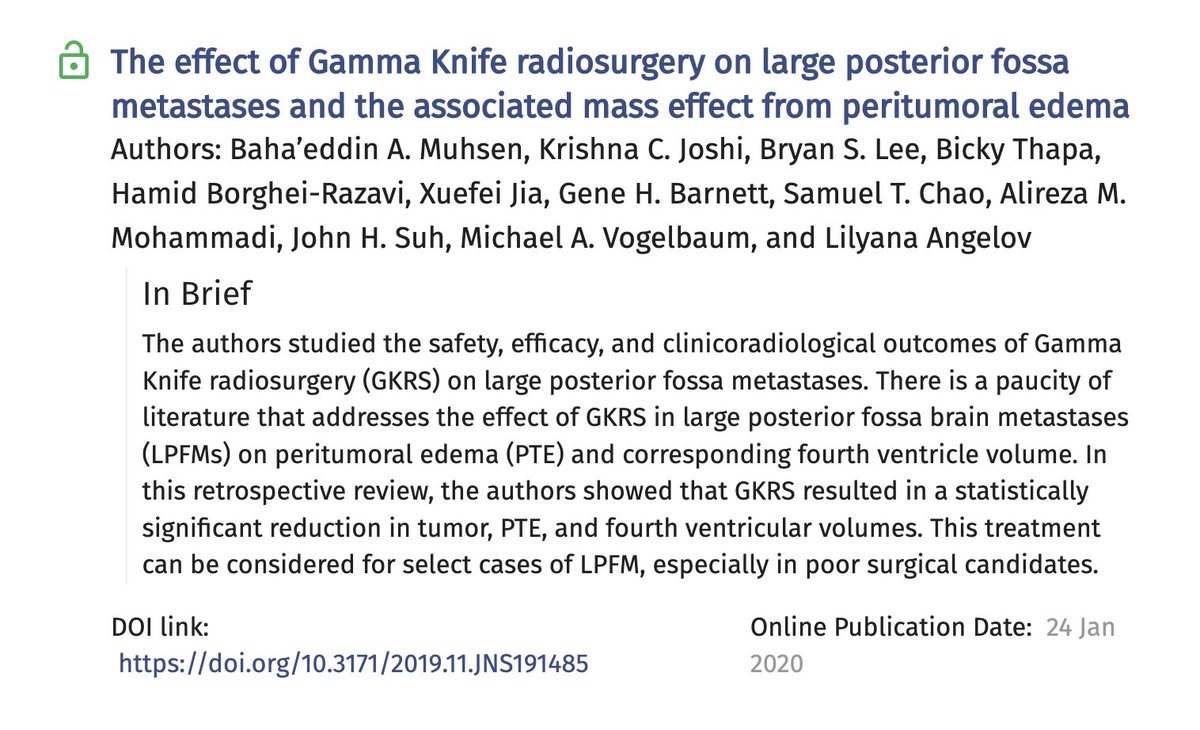

Krishna C. Joshi

@krishna5182

Endovascular fellow and Neurosurgery resident, Rush University Medical Center